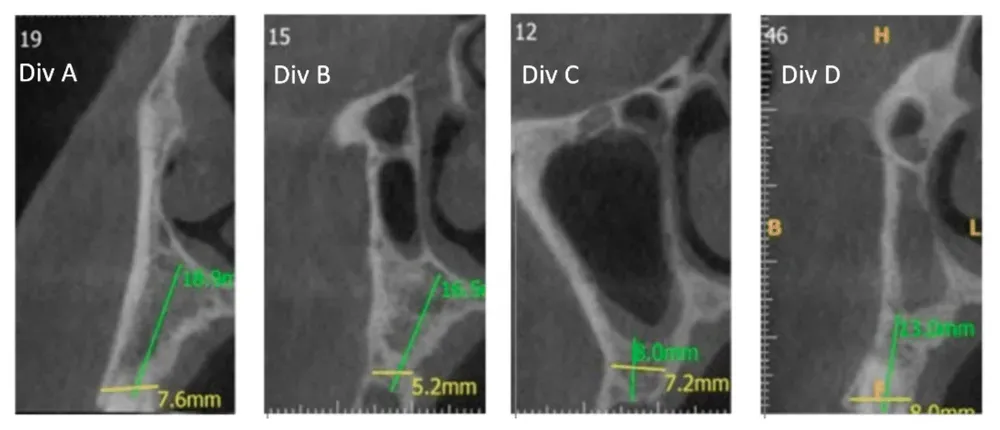

La distribuzione verticale rivela pattern ancora più interessanti, classificati dagli autori in divisioni. Vedi figura sotto.

Da sinistra a destra—Sezioni trasversali CBCT: Divisione A (Div. A): Cavità nasale da sola; Divisione B (Div. B): Cavità nasale adiacente alla cavità sinusale; Divisione C (Div. C): Cavità sinusale da sola sopra la cresta alveolare; Divisione D (Div. D): La cavità nasale è posizionata in posizione superiore rispetto alla cavità sinusale. Da Yahya et al. (2021). Licenza CC4.0.